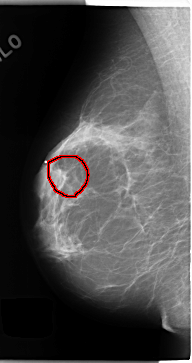

FILE: C_0149_1.RIGHT_MLO.OVERLAY

TOTAL_ABNORMALITIES 1

ABNORMALITY 1

LESION_TYPE MASS SHAPE OVAL MARGINS OBSCURED

ASSESSMENT 4

SUBTLETY 1

PATHOLOGY MALIGNANT

TOTAL_OUTLINES 1

BOUNDARY